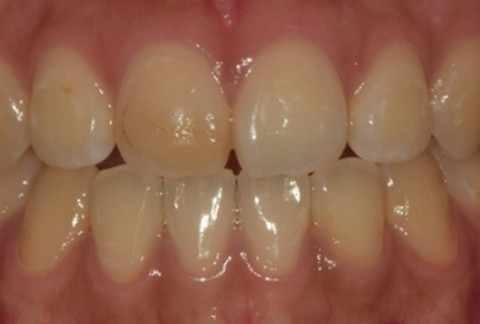

임플란트-전후사진